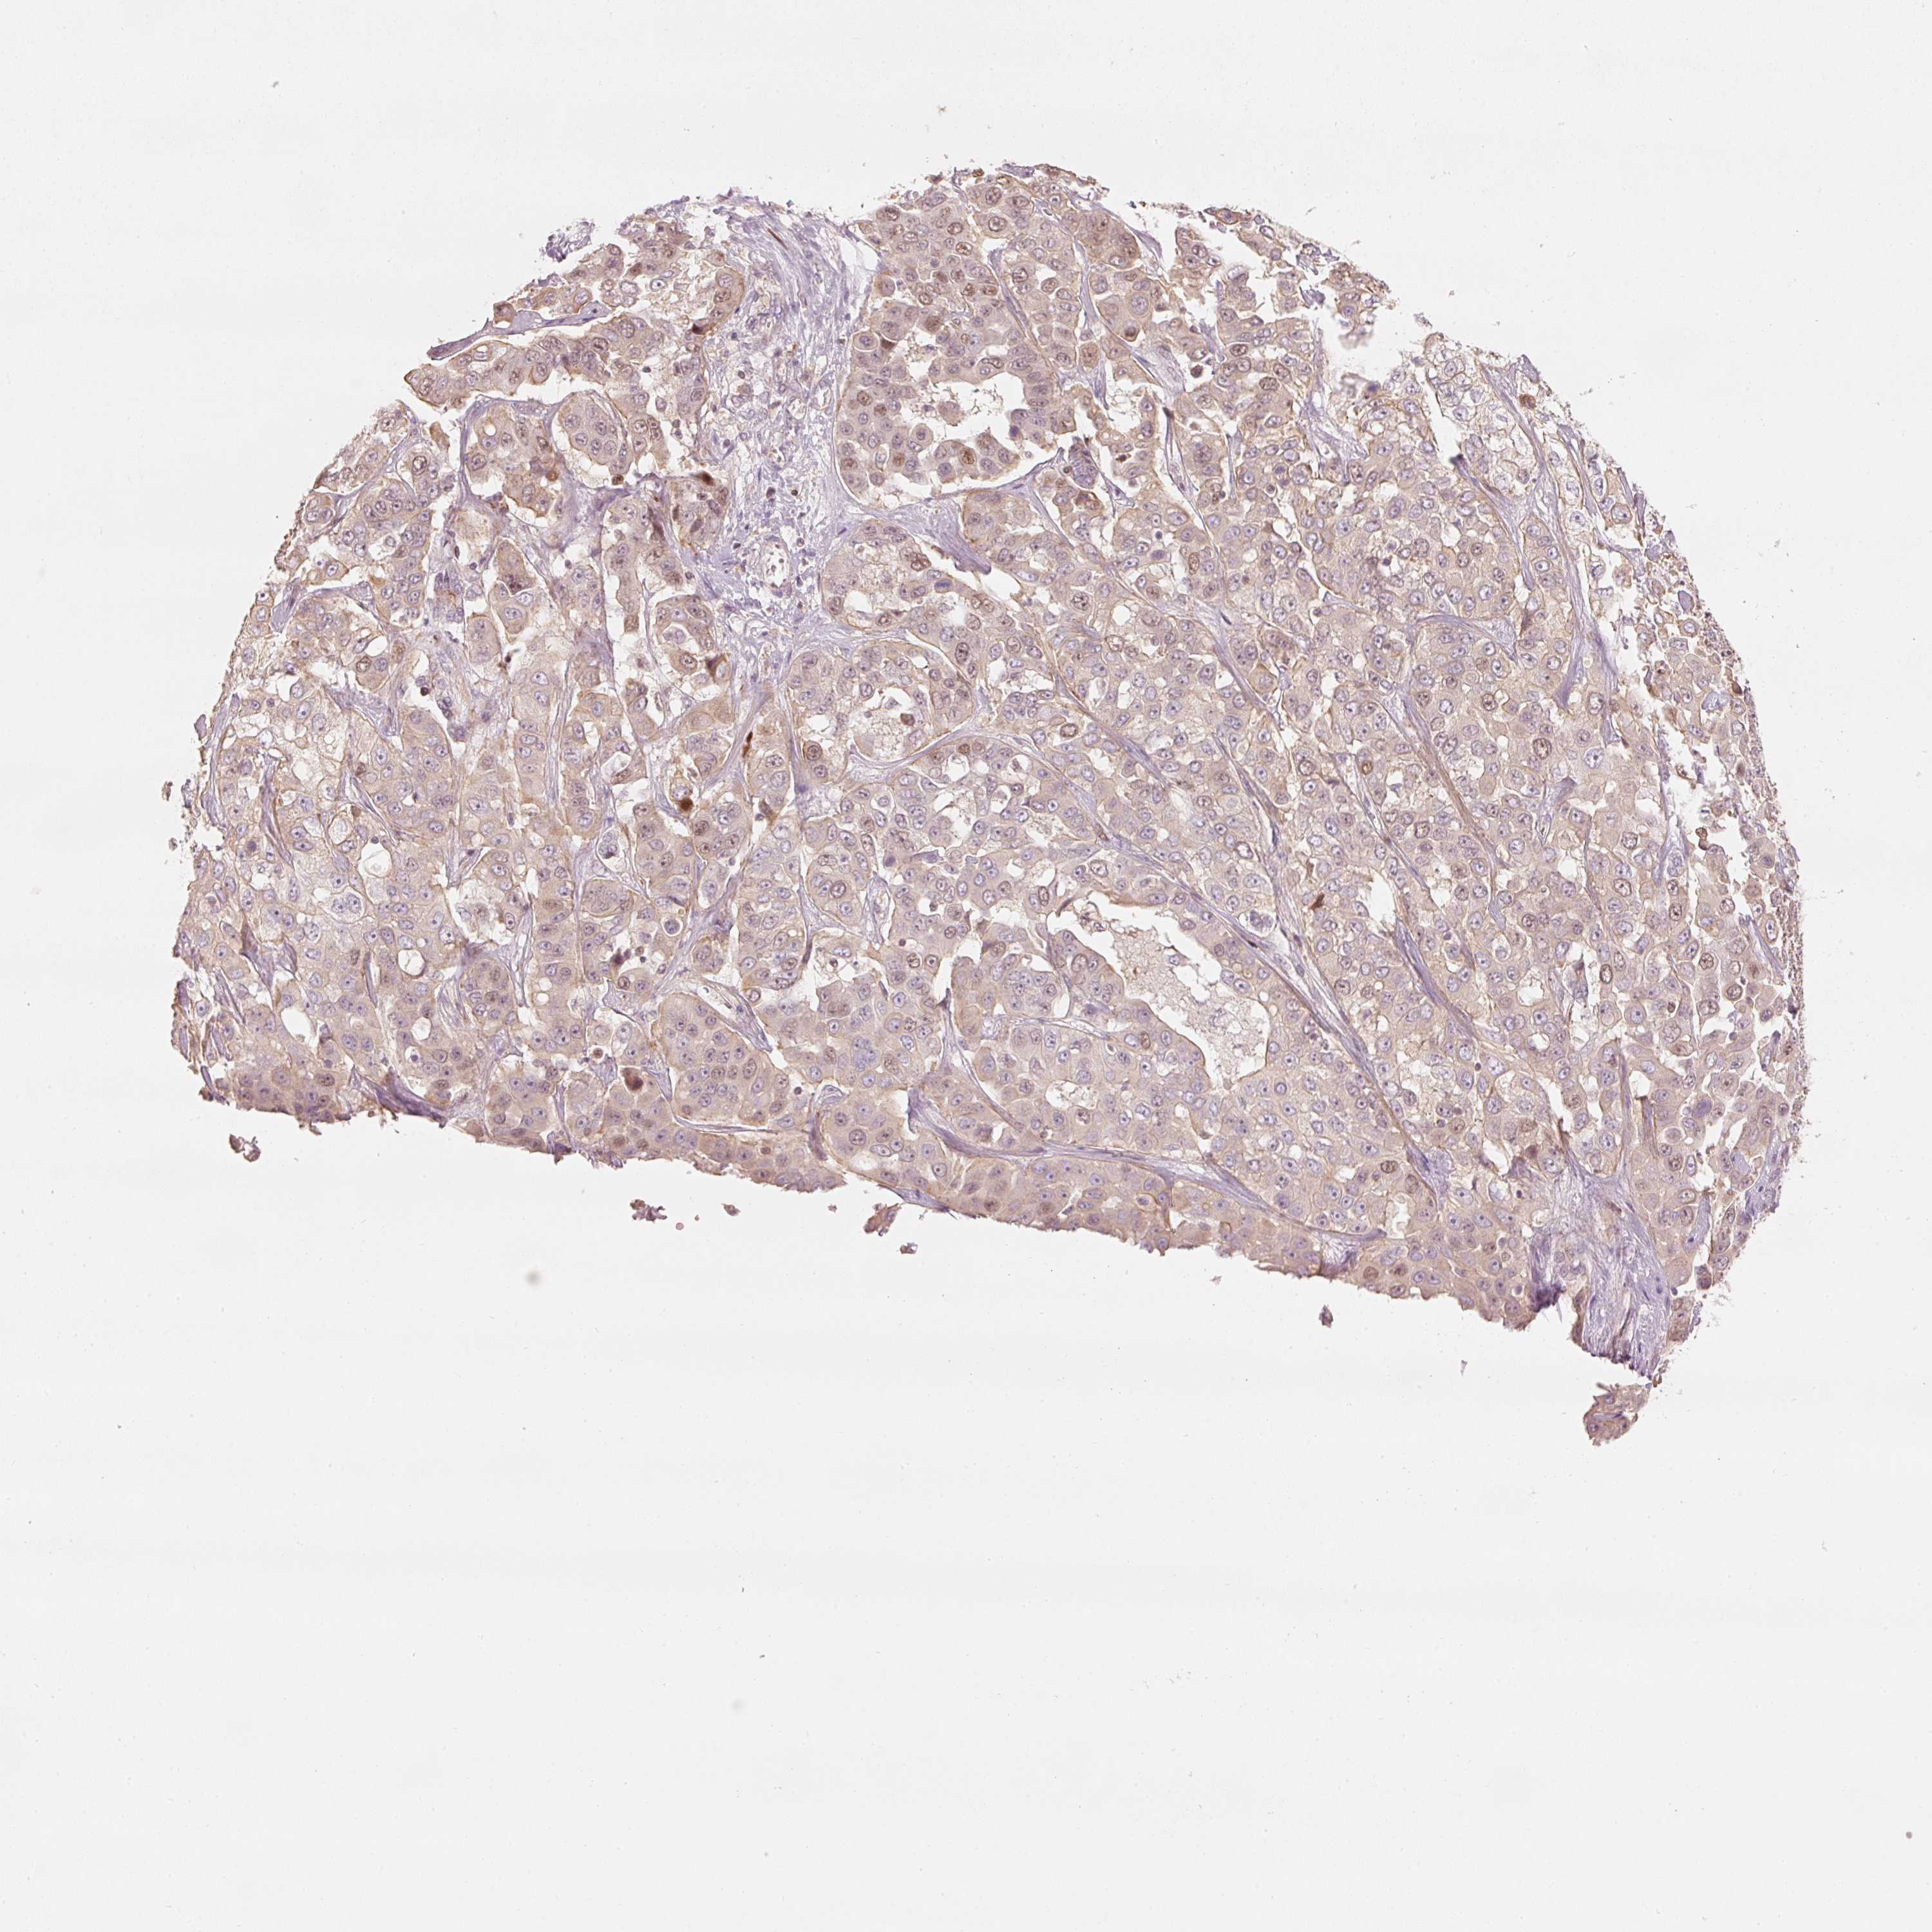

LIVER CANCER - Protein expressioni

A mouse-over function shows sample information and annotation data. Click on an image to view it in a full screen mode. Samples can be filtered based on level of antibody staining by selecting one or several of the following categories: high, medium, low and not detected. The assay and annotation is described here.

Note that samples used for immunohistochemistry by the Human Protein Atlas do not correspond to samples in the TCGA dataset.

Antibody stainingi

Antibody staining in the annotated cell types in the current human tissue is reported as not detected, low, medium, or high, based on conventional immunohistochemistry profiling in selected tissues. This score is based on the combination of the staining intensity and fraction of stained cells.

Each image is clickable and will lead to virtual microscopy that enables deeper exploration of all samples and also displays staining intensity scores, fraction scores and subcellular localization as well as patient and tissue information for each sample.

Antibody HPA054060

Staining

High

Medium

Low

Not detected

Intensity

Strong

Moderate

Weak

Negative

Quantity

>75%

75%-25%

<25%

None

Location

Nuclear

Cytoplasmic/membranous

Cytoplasmic/membranous,nuclear

Cholangiocarcinoma

Carcinoma, Hepatocellular, NOS